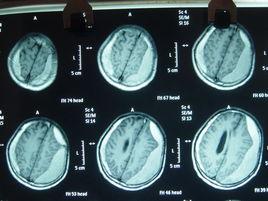

3.頭部X線攝片多顯示慢性顱內壓增高表現,少數可見血腫鈣化徵象。幕上血腫者,超音波檢查中線波向對側移位。腦血管造影、頭部CT或核磁共振檢查可顯示血腫部位和範圍。